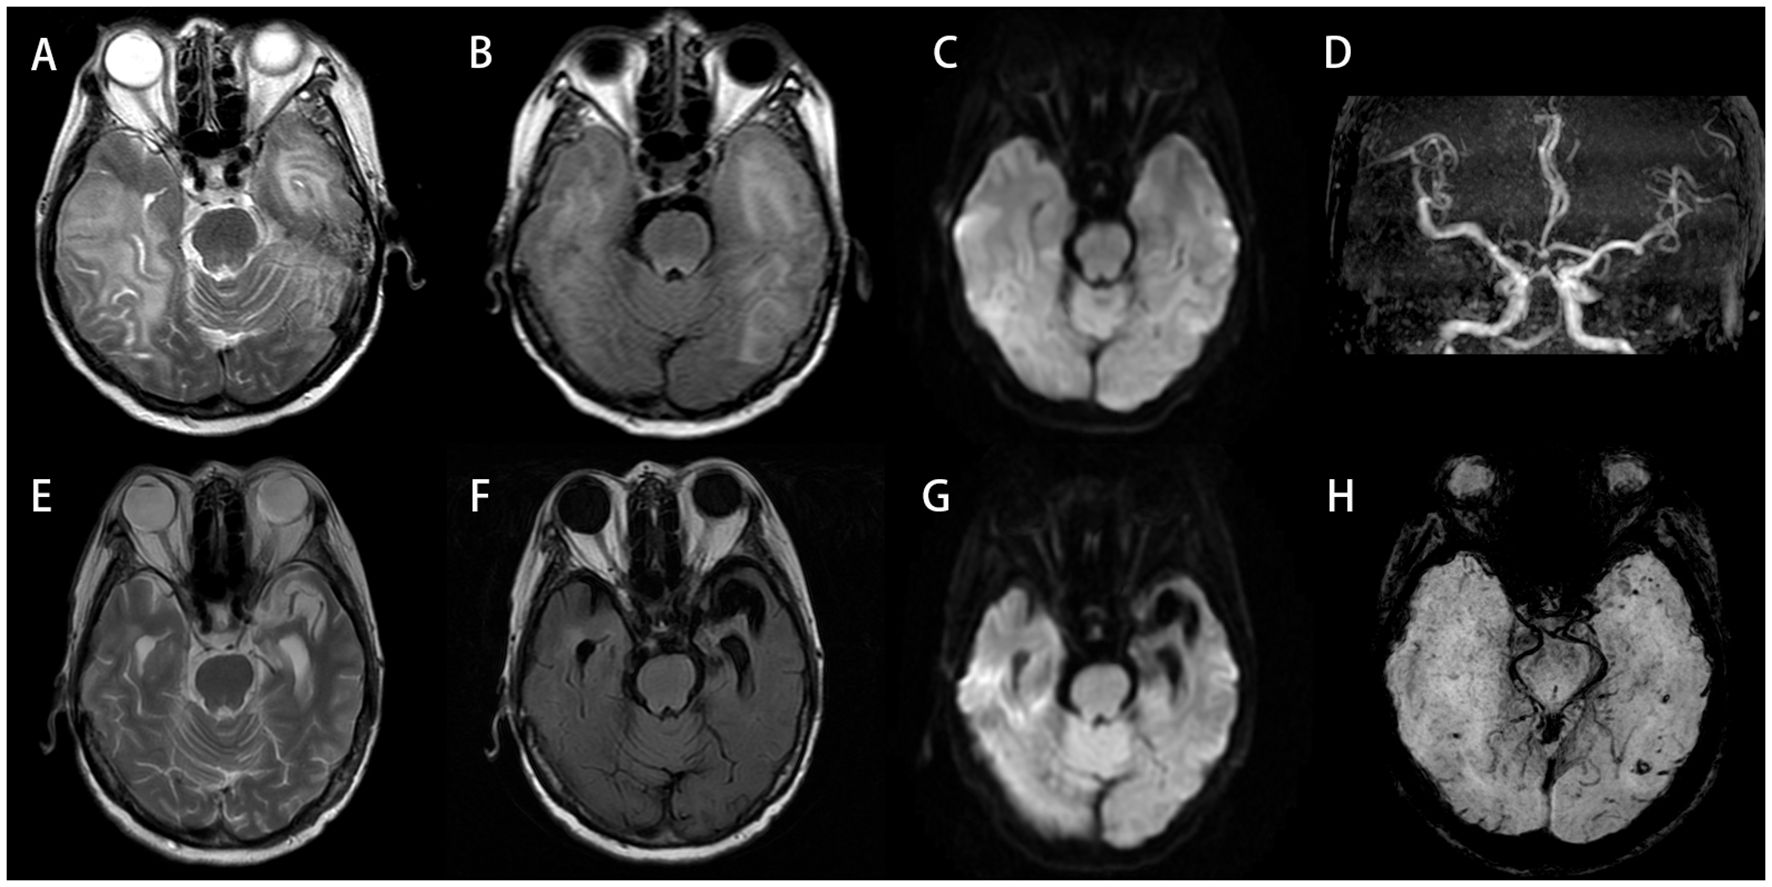

Electroencephalogram (EEG) demonstrated moderate diffuse abnormalities characterized by theta rhythm in the background activity and frontal-predominant sharp/slow waves. Magnetic resonance imaging (MRI) revealed extensive coalescing lesions in the bilateral parietal, temporal, and occipital lobes extending to the basal ganglia, exhibiting T1 hypointensity, T2 hyperintensity, and mild T2/FLAIR hyperintensity, but no hyperintensity on diffusion-weighted imaging (DWI) (Figures 1A–C). Vascular studies identified significant intracranial atherosclerosis, with magnetic resonance angiography (MRA) showing right middle cerebral artery M1-segment stenosis (Figure 1D), while magnetic resonance venography (MRV) confirmed left transverse/sigmoid sinus narrowing. Susceptibility-weighted imaging (SWI) detected scattered microhemorrhagic foci in temporal/occipital regions (Figure 1H). Perfusion-weighted imaging (PWI) demonstrated hemodynamic disturbances characterized by reduced cerebral blood volume (CBV) and cerebral blood flow (CBF) in the left frontal lobe, as indicated by an arrow, along with prolonged perfusion times in the right frontotemporal regions, evidenced by time to peak (TTP) and time to maximum (Tmax) parameters compared to the left side (Figures 2A–D). Magnetic resonance spectroscopy (MRS) of the right temporal lobe exhibited metabolic derangement with elevated choline and reduced N-acetylaspartate (NAA) peaks (Figure 2E).

Figure 1. (A–D, H) Initial scan (September 13, 2023). Bilateral temporal and occipital lobes demonstrate extensive abnormal signals: hyperintensity on T2-Weighted Imaging (T2WI) (A), with mild hyperintensity on T2/FLAIR (B), but no restricted diffusion on DWI (C). MRA reveals intracranial atherosclerotic changes, featuring segmental stenosis in the right middle cerebral artery M1 segment (D). SWI shows scattered punctate hypointensities in bilateral temporo-occipital regions, suggestive of microhemorrhages (H). (E–G) Follow-up scan (July 17, 2024; 10-month post-baseline): previous abnormal signals in bilateral temporo-occipital regions have largely resolved, with encephalomalacia formation in the left temporal lobe. DWI hyperintense areas exhibit interval expansion compared to September 2023 baseline. Significant progression of cerebral atrophy is noted. DWI, diffusion-weighted imaging; MRA, magnetic resonance angiography; SWI, susceptibility-weighted imaging.

One month after discharge, she returned for a follow-up appointment, reporting that she felt mentally well and had no issues. A follow-up MRI+DWI conducted on November 2, 2023, showed that the lesions in the temporal, parietal, and occipital lobes had decreased slightly in size compared to those in the previous scan on September 13, 2023. Ten months after discharge, another follow-up MRI+DWI indicated that the original abnormal signals in the bilateral temporal and occipital lobes had largely resolved; however, significant brain atrophy was observed (Figures 1E–G). At that time, the dosage of prednisone acetate had been reduced to 10 mg once daily, and cyclophosphamide was administered at 50 mg every other day. Aside from polyarticular pain and poor sleep, the patient did not report any other major issues.

MRI serves as a crucial tool for evaluating neurological symptoms in RA patients. Based on previous literature, CRV typically presents with multifocal intracranial white matter lesions affecting multiple lobes, most commonly the frontal, temporal, and occipital regions. Infarctions and hemorrhagic foci may coexist (1, 28). MRA reveals cerebral arterial narrowing and irregular contours indicative of stenosis/occlusion, which may lead to misdiagnosis as non-inflammatory vascular events (the imaging findings of 37 patients are summarized in Supplementary Table 3). Notably, our representative case showed confluent bilateral temporo-occipital lesions involving both white and gray matter. This cross-territorial distribution pattern helped exclude cerebral infarction during initial differential diagnosis (Figures 1A, B). MRA demonstrated stenosis in the M1 segment of the right middle cerebral artery (Figure 1D). CRV may mimic infectious or neoplastic processes but typically shows minimal/no enhancement and lacks significant mass effect despite extensive involvement, serving as key differentiating features.

In addition, in the diagnostic evaluation of RA patients with CNS symptoms, RM represents a critical entity to distinguish from CRV (3234). Although both conditions can present with overlapping clinical features, their underlying pathophysiology and radiological signatures differ (22, 34). CRV primarily manifests as parenchymal injury and the characteristic “string-of-beads” stenosis on MRA (22). In contrast, RM involves inflammation and rheumatoid nodule deposition within the meninges (10). Accordingly, RM typically exhibits leptomeningeal or pachymeningeal enhancement on post-contrast T1-weighted MRI, often predominant in the frontoparietal regions (35). A recently described imaging clue for RM is the “mismatch DWI/FLAIR” sign, which refers to patchy diffusion restriction without corresponding FLAIR hyperintensity (10, 33). Notably, this mismatch pattern was reversed in our case: the cerebral lesions showed significant T2/FLAIR hyperintensity but no hyperintensity on DWI. This fundamental difference in imaging underscores the radiologic distinction between the two entities. Therapeutically, while both conditions require immunosuppression, RM often shows a favorable response to high-dose corticosteroids and conventional Disease-Modifying Antirheumatic Drugs (DMARDs) (36, 37), whereas CRV may necessitate more aggressive regimens, such as cyclophosphamide. Therefore, incorporating RM into the differential diagnosis is essential for guiding appropriate imaging interpretation and treatment selection.